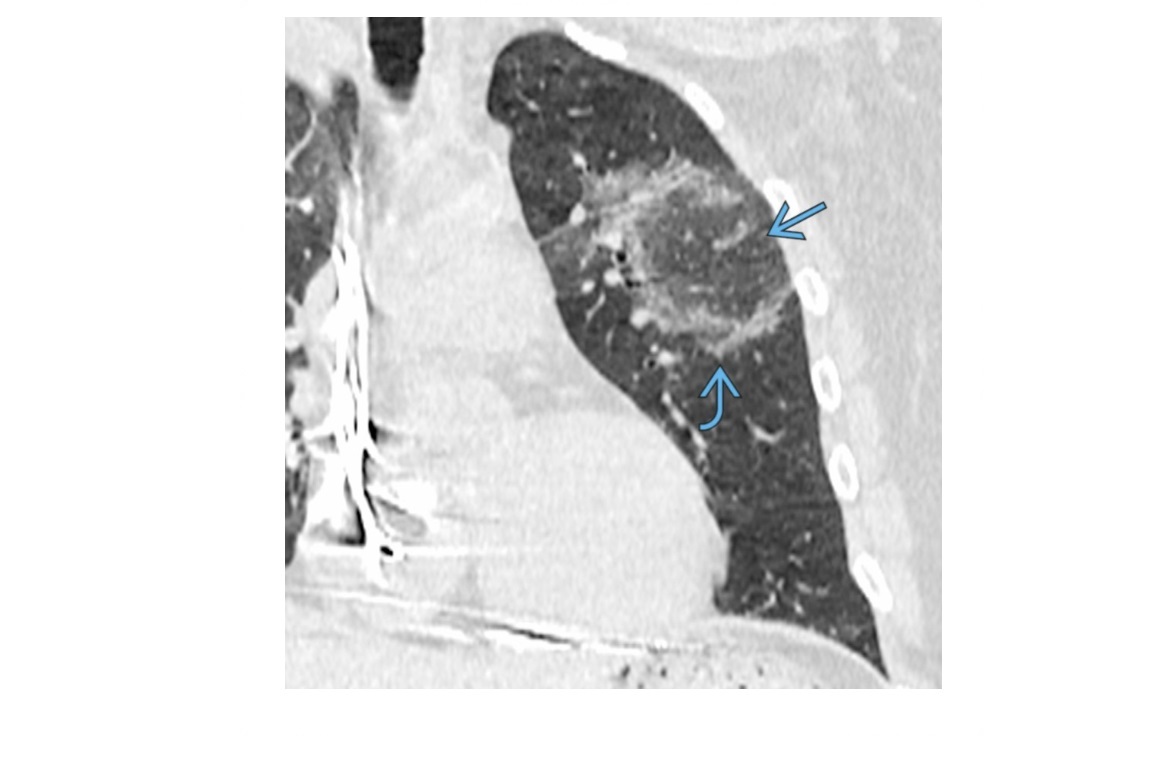

NSIP

lower lung zone predominant

CXR

bilateral, reticular opacities

CT

Absent (less) / microcystic honeycombing

Bilateral ground-glass &/or reticular opacities

Traction bronchiectasis/bronchiolectasis

Relative Subpleural sparing

peribronchovascular fibrosis

Most hunt for assocation/cause on CT

?dilated oesophagus - scleroderma

? joint disease - RA

?portcath/PICC - chemotherapy

sjorgens

HIV